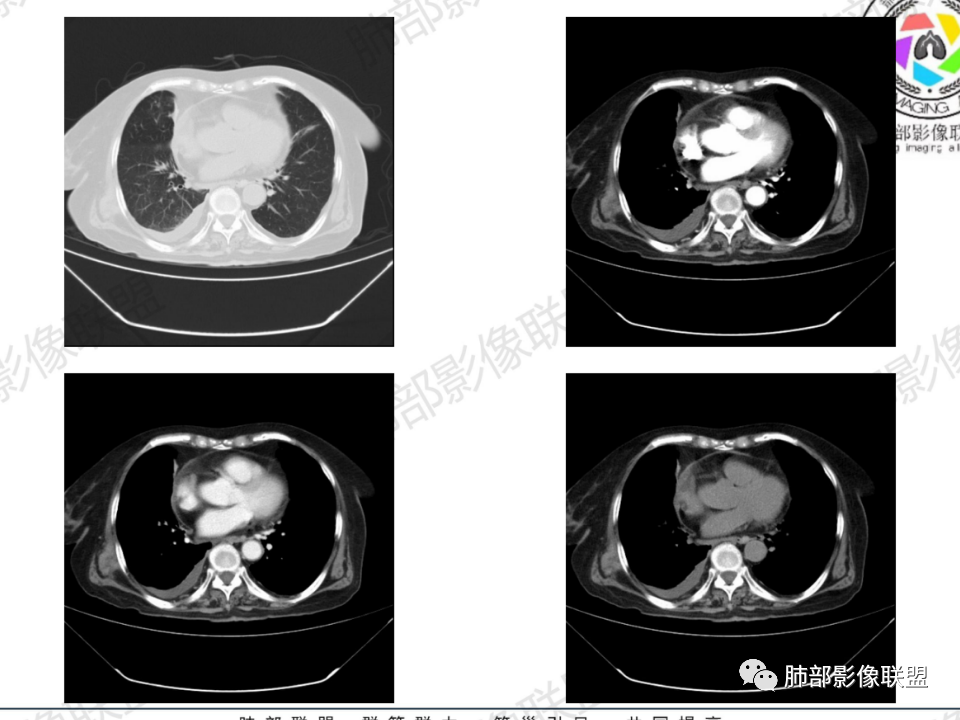

老年患者,病程中等,有咳嗽/喘息/低热症状,肿瘤标志物升高,感染标志物不高,右上肺新生物,中央型,边界清楚,有分叶,支气管截断,内有坏死,不均匀强化,考虑肺癌,鳞癌?

那个人:老年女性,亚急性病程,咳嗽发热。有垂体前叶功能减退,目前激素替代治疗,长期激素,量小,不知道累积量,没有目前激素水平指标。既往有淋巴结结核病史。肿瘤标记物Ca125升高。血沉升高,C反应蛋白轻度异常。影像,右肺上叶靠近肺门团块影,右肺门淋巴结钙化肿大,支气管狭窄,局部增厚,团块影外朝内改变,强化明显,血管破坏不明显,有粘液。和纵隔胸膜分界清楚,周围肺组织有斑片渗出影,右侧胸腔积液,考虑炎性?结核?支气管镜检查除外恶性飞鹰行动:老年患者,影像表现 右肺上叶占位性病变,边界清楚,有分叶征,内见细小钙化,右肺上叶支气管截断,增强病灶不均匀强化,病灶内有条状坏死区(扩张的支气管?),纵膈内未见增大淋巴结,考虑炎性病变,结核可能。一切∮随缘:右肺上叶实性肿块形态不规则,呈三角形,边缘分叶,边界伴有磨玻璃影,近段支气管未见明显显示,可能堵塞,病变平扫密度均匀,增强后可见低密度坏死无强化,周围略强化,右肺下叶散在结节。心包积液,及右侧胸腔积液,临床:有低热,低蛋白血症,肿瘤标记物高,考虑恶性:腺癌,神经内分泌癌(强化偏弱了),淋巴瘤,鉴别:结核红星:老年女性患者右肺上叶,肺门上区 分叶状肿块 ,右肺上叶支气管显示不清,增强扫描肿块,中等程度强化可见小斑片状坏死区,病灶内部可见斑点状钙化灶,病灶周围可见斑片状及小斑点状影,纵膈淋巴结增大,其他区域,胸膜下可见斑点状钙化。考虑肉芽肿性病变,结核的可能性大。老年患者最排除肿瘤性病变腺癌。土娃:右上肺不规则肿块影,边缘分叶,边界磨玻璃影欠清,病灶分叉状,内见点状钙化影及坏死灶,支气管堵塞,病灶增强强化不明显。考虑瘤样结核,鉴别淋巴瘤。张小兵:老年女性,亚急性病程,右肺上叶见不规则肿块,边缘平直凹陷为主,周围GGO边界不清,内见点状钙化及坏死灶,增强持续性渐进强化,右侧少量胸腔积液,双肺门及纵隔肿大淋巴结伴钙化,综合考虑慢性炎症。saf:老年患者,影像表现 右肺上叶占位性病变,边界清楚,有分叶征,增强病灶明显不均匀强化,纵膈内未见增大淋巴结,考虑炎性病变,结核可能。小兜:老年女性,咳嗽喘息一月,发热三天,肿瘤标志物升高,长期激素替代治疗。CT示右肺上叶近肺门不规则实变影,周围伴磨玻璃影,增强持续性渐进强化,内部血管破坏不厉害,内部可见多发条形低密度灶,右侧胸腔可见少量积液,双肺门及纵隔可见钙化淋巴结,考虑为炎性病变,结核可能玫:女,79咳嗽,喘息一月,发热三天入院,右肺上叶不规则形软组织密度肿块影,边界清晰,边缘见分叶及细短毛刺,病灶内见点状钙化影及稍低密度区,病灶边缘呈磨玻璃样改变,增强扫描,病灶呈不均匀性强化,考虑炎性病变,鉴别鳞癌。大雄:老年女性,既往诊断淋巴结结核,提示已治愈,近2年服用激素,诱导结核复燃→发热;纵隔肺门淋巴结肿大钙化,压迫支气管,右肺上中下叶支气管均狭窄→喘息咳嗽;尖段支气管受累闭塞→肺不张、支气管粘液栓;累及胸膜,结核性胸膜炎并胸水→右侧胸痛;实验室,血沉快,CA125高,低蛋白,符合;下一步,支气管镜尖段支气管刷检抗酸染色周太狼:老年女性,亚急性病程,肿瘤标志物升高。CT示右肺上叶尖段不规则肿块影,有分叶、收缩,周围伴磨玻璃影,增强渐进强化,内部可见多发条形低密度灶,右侧胸腔及心包少量积液,纵隔内淋巴结稍增大。倾向于恶性病变,肺癌伴阻塞性炎变可能。丽:老年女性,右肺上叶不规则软组织肿块,边缘清晰,内密度不均,可见点状钙化及粘液栓,周围可见片状高密度影,增强后均匀强化,内多发低密度,纵膈多发钙化淋巴结,考虑结核可能大,建议结合支气管镜检查除外肿瘤宇宙:右胸廓缩小,右肺上叶团块影及不张,平直边,周围磨玻璃影,纤细胸膜牵拉,上叶尖段支气管堵塞,明显延迟强化,可见支气管粘液栓,两肺门钙化淋巴结,右侧胸水,考性炎性肉芽肿,鉴别腺癌王秀仙:右肺上叶肺门区肿块,上叶支气管开口阻塞,形态不规则,密度不均,内可见支气管粘液栓及多发小灶性坏死,周围磨玻璃影边缘模糊,渐进强化,右侧胸腔积液、胸膜钙化,考虑炎性肉芽肿性病变,慢性炎症。鉴别鳞癌,结核。刘丹:老年女性,右肺上叶肿块伴钙化,右肺上叶支气管截断,增强后均匀强化,周边可见点片状模糊影,右侧胸腔积液,右肺门淋巴结增大,考虑占位并阻塞性炎症,肿瘤?结核?建议纤支镜检查。小飞:右肺上叶纵隔旁软组织肿块,边缘深分叶、长毛刺及毛刷样短毛刺,边缘磨玻璃影,磨玻璃边界模糊,支气管截断,平扫密度不均,可见点状钙化,增强不均匀明显强化,心影增大,心包积液,右侧胸腔积液,考虑恶性肿瘤,腺癌?秦化君:右肺上叶不规则分叶软组织密度肿块,边缘清晰,胸膜牵拉,周围花花草草,上叶尖段支气管阻塞,内可见点状钙化,增强后密度不均可见支气管粘液栓及坏死区,内见血管分枝。中间段及中叶,下叶支气管狭窄,壁见钙化。右肺门淋巴结肿大,右侧胸腔积液,心包粘连肥厚。考虑1右上肺恶性病变,鳞癌?2右肺多叶段支气管狭窄,考虑支气管内膜结核?3胸腔积液及肺门淋巴结肿大,转移?风儿:老年女性,右肺上叶肿块,形态不规则,外围大内带小,边缘分叶膨隆平直及毛糙,密度不均,内见支气管粘液栓及多发小灶性坏死,坏死边缘清晰 ,渐进强化,上叶尖段支气管阻塞,叶支气管壁有局限性增厚,邻近胸膜腔微积液;纵隔及双肺门淋巴结肿大,部分钙化,右侧胸腔积液、心包积液、胸膜钙化,考虑炎性,肉芽肿性结核可能性大。鉴别鳞癌,女性及血供均不支持;腺癌,坏死边界太清晰。流心明智:老年女性,79岁,咳嗽、气短1月,发热3天。胸CT:右肺上叶见不规则肿块,边缘有膨隆、有平直凹陷,周围GGO边界不清,病灶内见点状钙化、粘液栓,尖段支气管未见,增强持续性渐进强化,右侧少量胸腔积液,双肺门及纵隔肿大淋巴结伴钙化,肺动脉增粗。考虑:右上叶尖段堵塞并慢性炎症,支气管TB并结石?鉴别Ca

右肺体积小,提示既往结核

支气管影

前,后段都在,没有堵塞

支气管壁增厚,周围磨玻璃边界不清,提示炎症。胸膜下钙化符合结核

近期发热符合感染

这个层面往上应该是尖段,显示不清

背段支气管周围增厚伴钙化,符合结核改变

胸腔积液并胸膜钙化,符合结核;

结核是肯定有。现在最大问题是尖段

近端显示不清,但是远端是粘液栓,可以认为是还行的

如果是近端鳞癌,远端应该会堵塞,不会整个肿块里面还有较为通畅的支气管

这个区域我们看到密度与周围一致,并不是肺癌伴周围不张的感觉,所以鳞癌暂时是不支持的

临床信息:老年女性,亚急性病程,咳嗽发热。有激素使用史。既往有淋巴结结核病史。肿瘤标记物Ca125升高。血沉升高,C反应蛋白轻度异常。 影像所见:右侧胸廓相对狭小,右肺上叶不规则团块影贴附纵隔旁,轻度分叶,整体密度较均匀,偶见钙点。

相应上叶尖端及前段支气管开口未能追踪(阻塞),开口处见钙化。病灶渐进性强化,并衬托出较完整尖段及前段含液支气管影。支气管开口区域未见异常高密度强化(如类癌等)及相对乏血供区(如鳞癌)。病灶区未见液化坏死。右上纵隔及胸廓入口区未见病灶胸膜外突破(栽赃)。

右肺上叶后段等区域散在片状影,边界不清(提示渗出性病灶)。

纵隔及双肺门见钙化淋巴结。心包积液,右侧胸腔积液(提示存在活动新病灶)。双侧胸膜下见多发斑点状钙化,胸廓变形(提示存在结核基础病变可能)。 诊断意见:综上,右肺上叶块状影更符合继发性肺结核。 最后小结:既往诊断淋巴结结核,提示已治愈。近2年服用激素,可疑诱导结核复燃,也可引起发热。纵隔肺门淋巴结肿大钙化,压迫支气管,右肺上中下叶支气管均狭窄,所以引起喘息咳嗽。尖段支气管受累闭塞,导致肺不张、支气管粘液栓,出现条状无强化区。病变累及胸膜,导致结核性胸膜炎并胸水,引起右侧胸痛。实验室检查血沉快,CA125高,低蛋白,均符合结核。下一步,建议支气管镜尖段支气管刷检并抗酸染色。(本段摘自於雄老师精彩发言)